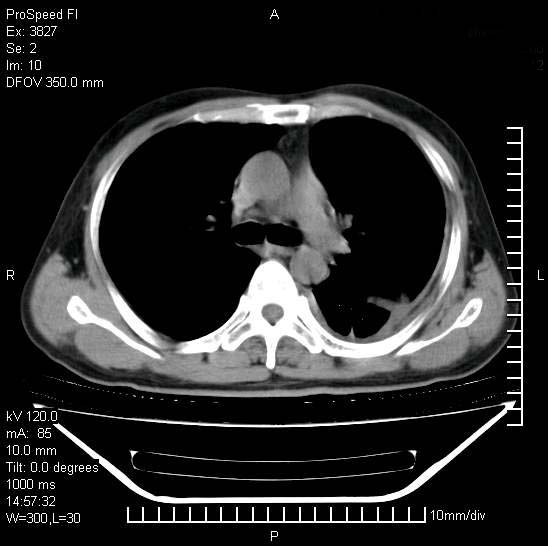

男性,一月前出现右侧肋区疼痛,较剧烈,干咳,无发热,自诉使用抗炎药后缓解,几天前又出现左侧剧烈疼痛,

发热,体温38。9,今天ct,考虑左侧包裹性脓胸,胸腔积液,右上中肺小斑片影,结核/炎症?胸水未见恶性细胞。